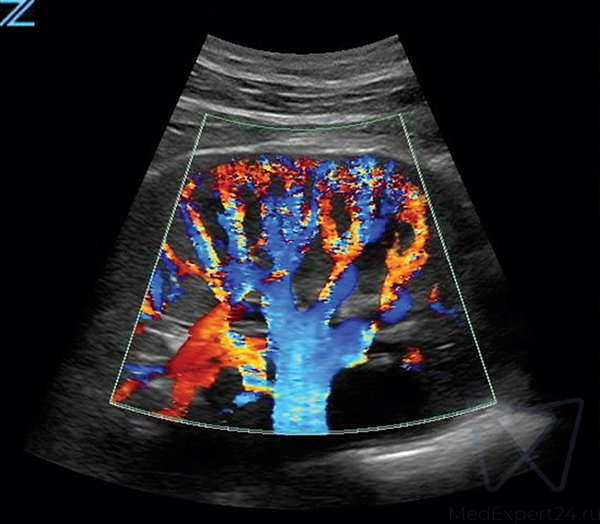

Система Zonare ZS3 оснащена инновационной программной технологией ZONE Sonography Technology (ZST), обеспечивающей диагностические преимущества в любых клинических ситуациях. Сфокусированное по всей глубине сканирования, четкое и детализированное изображение в В-режиме в сочетании с визуализацией в доплеровском режиме, позволяют охватить весь спектр клинических потребностей. УЗИ аппарат премиум класса подходит для проведения качественных исследований в любых условиях, благодаря быстрому переключению режимов и эргономичной, легкой портативной конструкции.

- Триплексный режим, с возможностью сохранения и просмотра кинопетли,

- Возможность выполнения контрастной эхографии с использованием абдоминальных датчиков и датчика для малых органов,